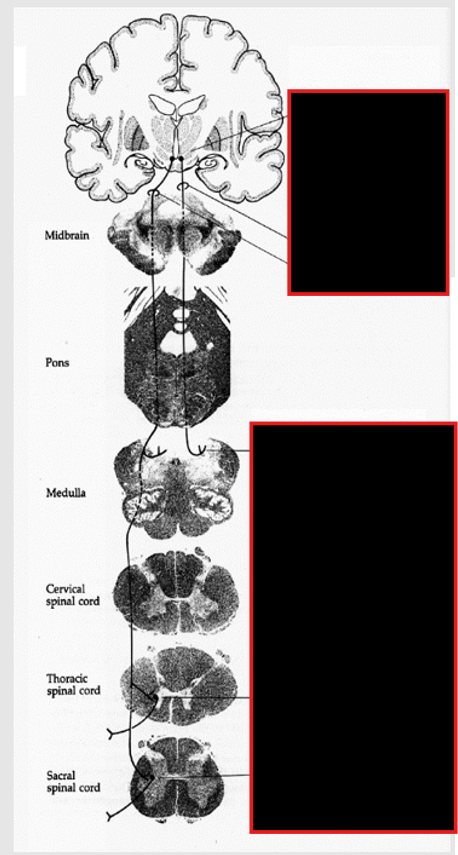

Pons Development:

derived from:

rhombencephalon (primary brain vesicle)

later as part of metencephalon along w/ cerebellum.

Location:

pontine flexure btw metencephalon and myelencephalon.